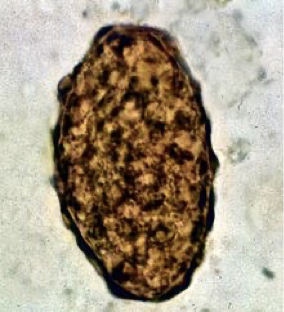

Pinworm eggs

Ascaris lumbricoides fertilized

Ascaris lumbricoides unfertilized